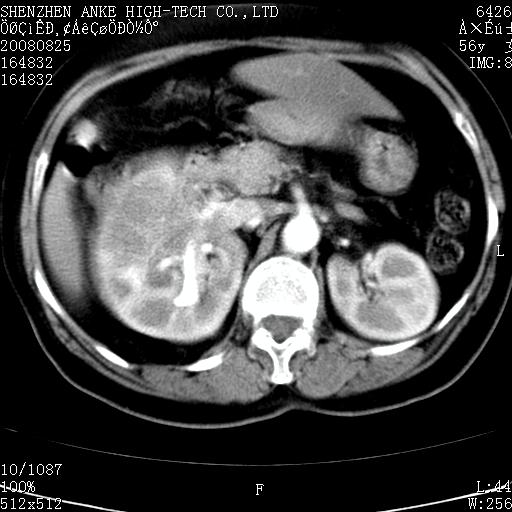

标题: CT15386:女性,56岁,腰痛3年 [打印本页]

患者,女性,56岁,腰痛3年,查:右腹部约8x10cm肿块,固定,无压痛;8月23日在外院做了平扫,发现右肾巨大肿块(外院具体诊断不祥);今天在我院做了静脉肾盂造影,示:右肾明显增大,分泌功能明显减弱。

1)考虑右肾癌并右肾静脉瘤栓形成。2)脂肪肝。